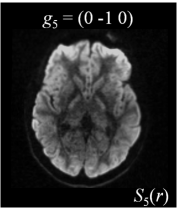

Six axial DW measurements and one non-DW image are shown in Figure 1, along with the corresponding magnetic field gradients . Note the difference in intensity values for different gradient directions.

| (a) | (b) | (c) | (d) |

![]() |

| (e) | (f) | (g) | (h) |